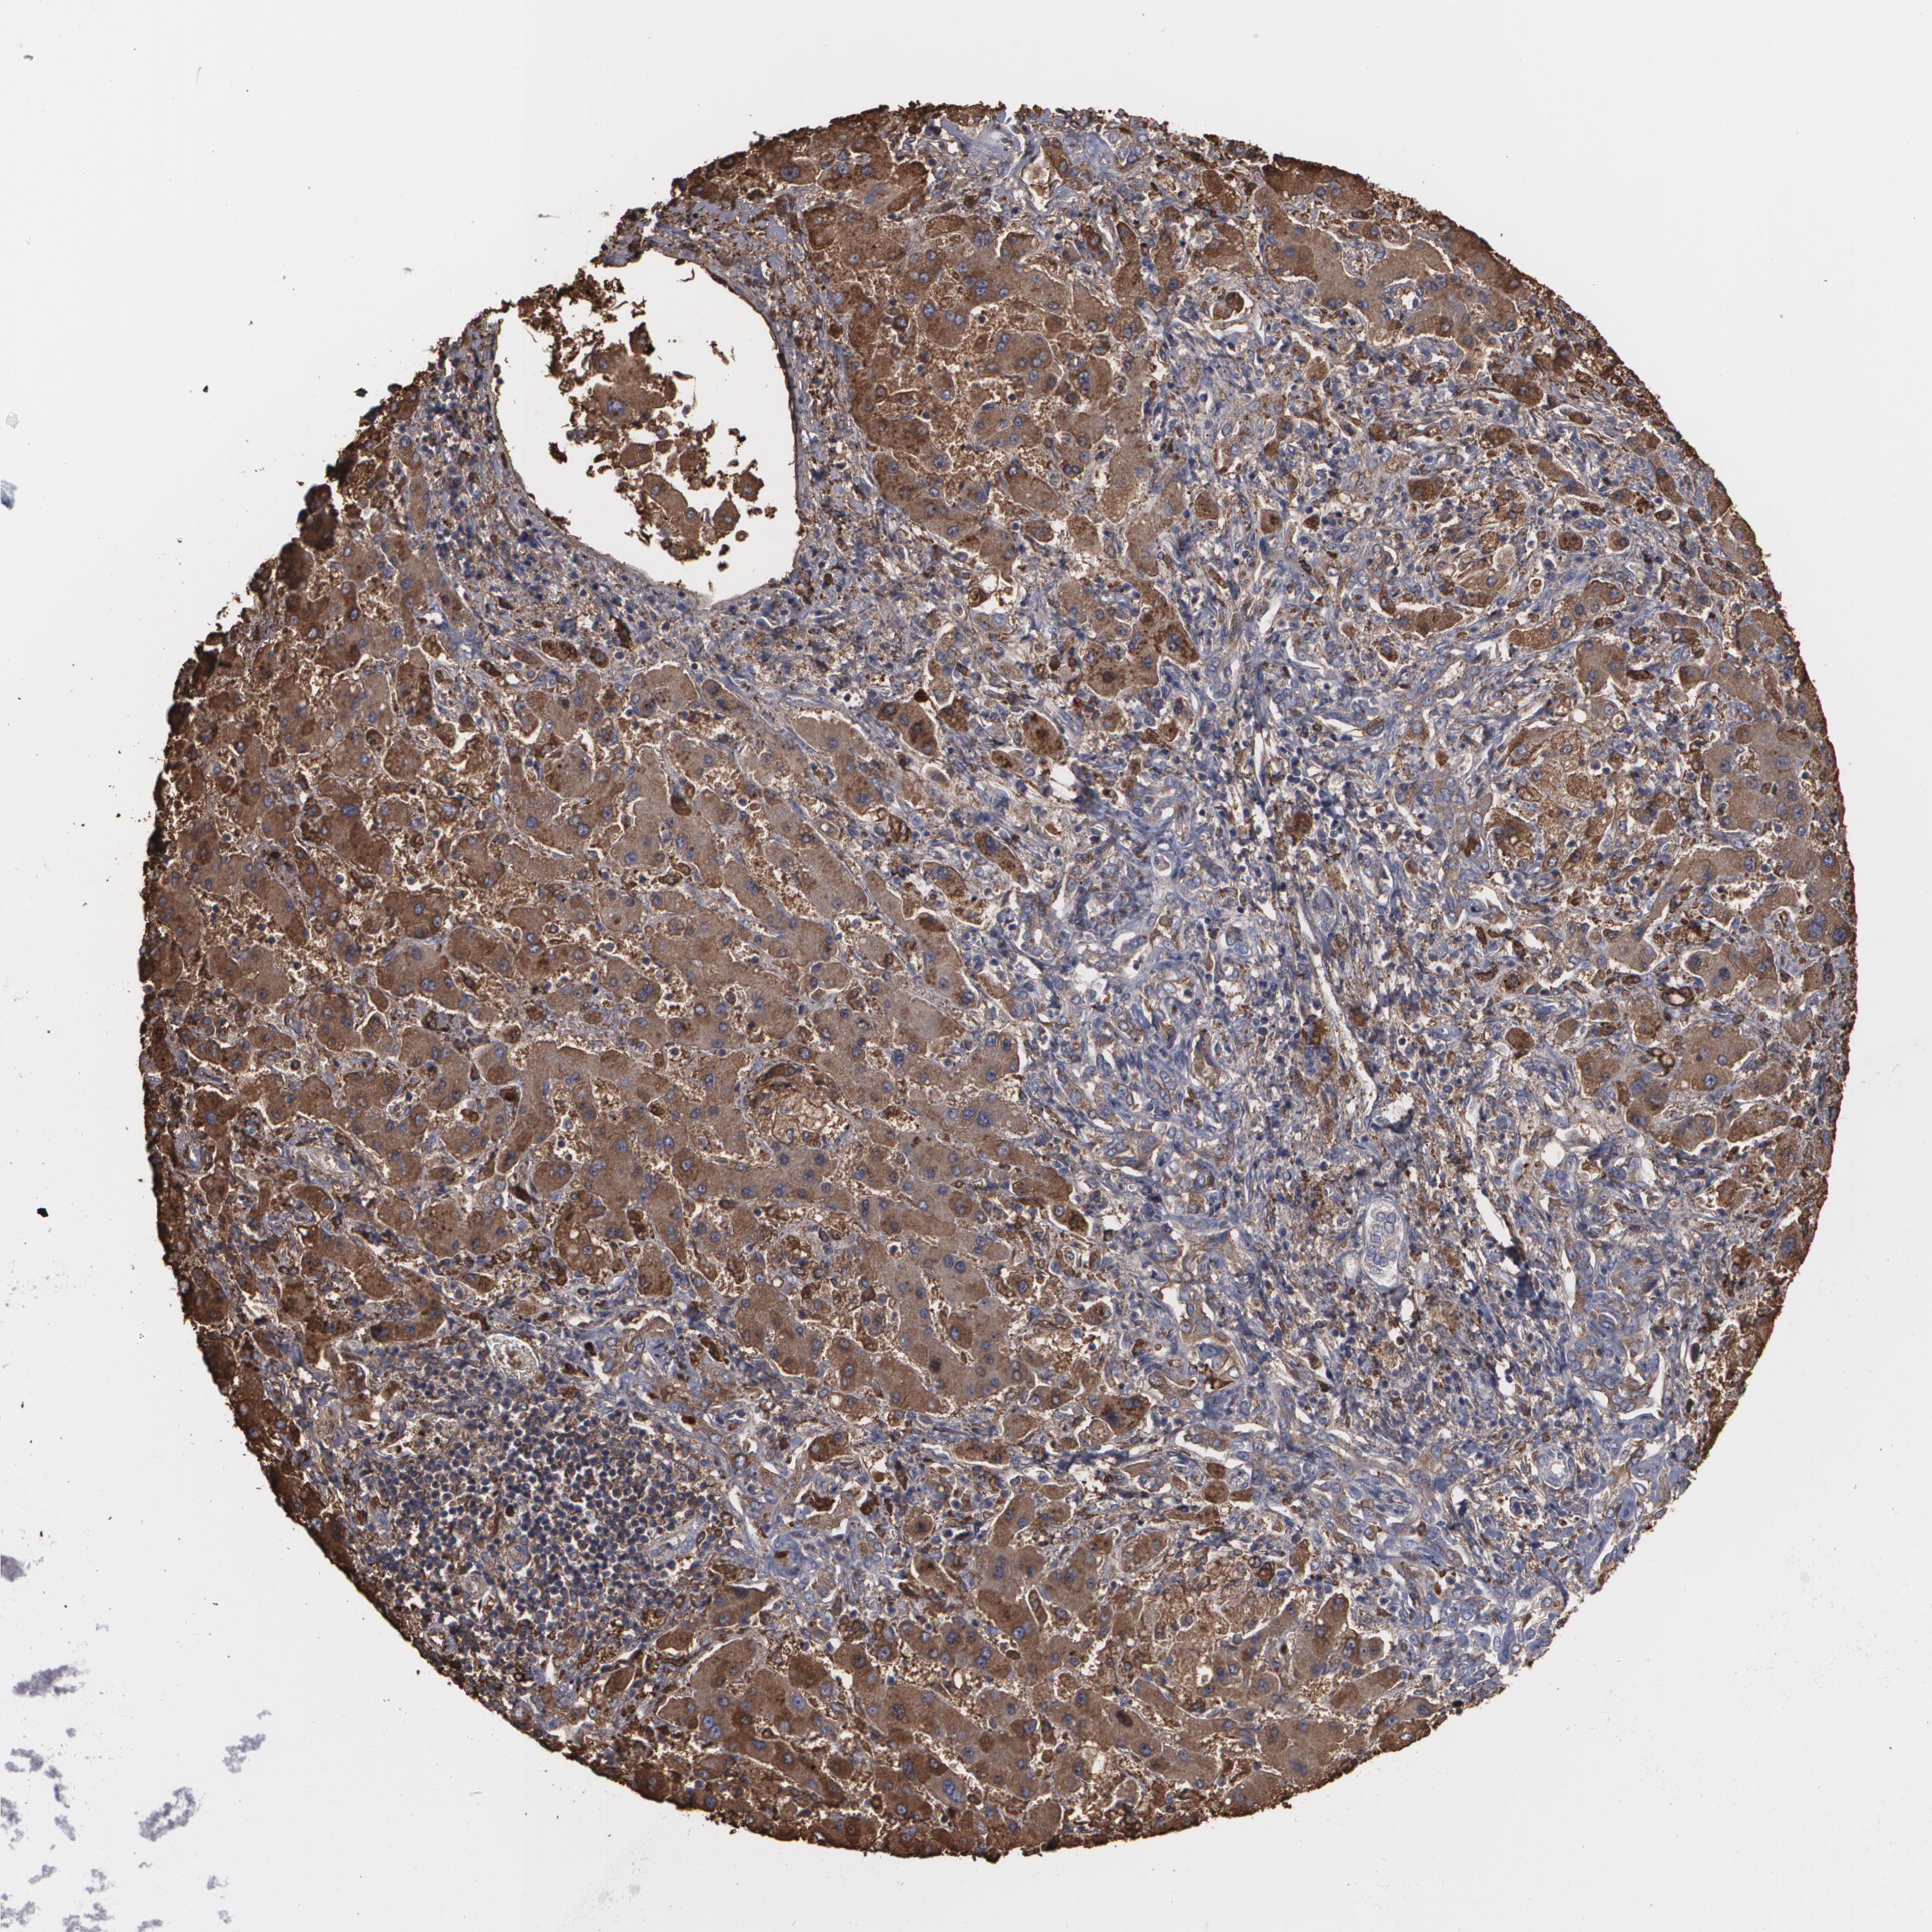

LIVER CANCER - Protein expressioni

A mouse-over function shows sample information and annotation data. Click on an image to view it in a full screen mode. Samples can be filtered based on level of antibody staining by selecting one or several of the following categories: high, medium, low and not detected. The assay and annotation is described here.

Note that samples used for immunohistochemistry by the Human Protein Atlas do not correspond to samples in the TCGA dataset.

Antibody stainingi

Antibody staining in the annotated cell types in the current human tissue is reported as not detected, low, medium, or high, based on conventional immunohistochemistry profiling in selected tissues. This score is based on the combination of the staining intensity and fraction of stained cells.

Each image is clickable and will lead to virtual microscopy that enables deeper exploration of all samples and also displays staining intensity scores, fraction scores and subcellular localization as well as patient and tissue information for each sample.

Antibody HPA001536

Antibody CAB035996

Staining

High

Medium

Low

Not detected

Intensity

Strong

Moderate

Weak

Negative

Quantity

>75%

75%-25%

<25%

None

Location

Nuclear

Cytoplasmic/membranous

Cytoplasmic/membranous,nuclear

Cholangiocarcinoma

Carcinoma, Hepatocellular, NOS